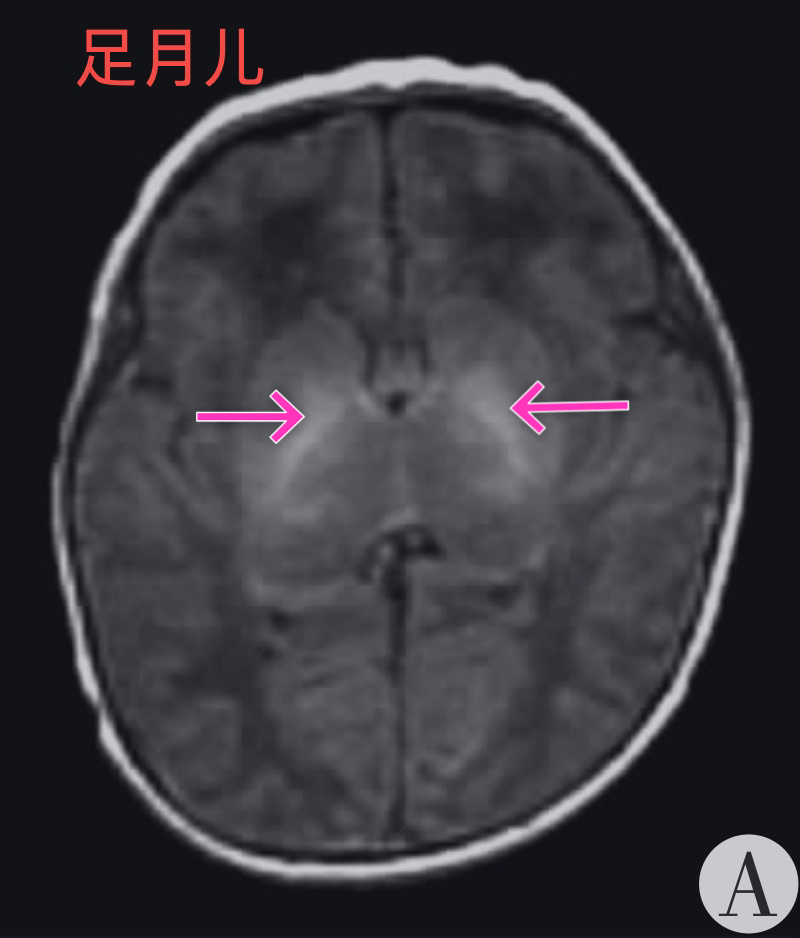

双侧苍白球可见t1wi高信号,t2wi高信号区域,无占位效应.